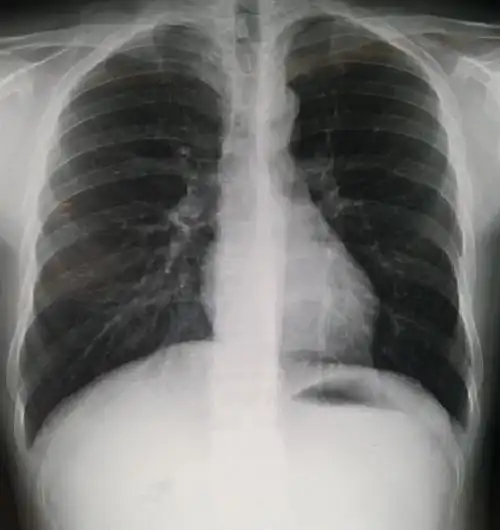

桶状胸,胸廓接近正方形,明显肺气肿

(前胸壁严重整体前突,外观为桶状)(重度桶状胸,严重胸廓畸形)入院查体

今天的wenlin手术:桶状胸的微创治疗方法